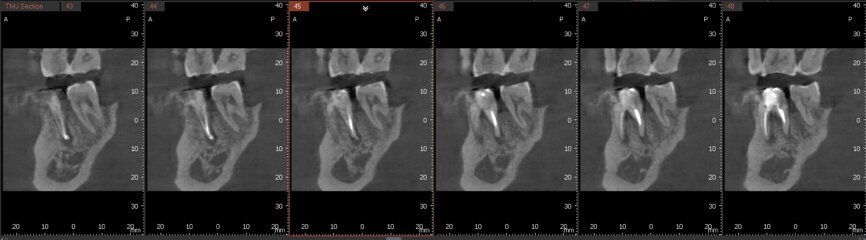

Fig.2a: Pre-op CBCT images of tooth #46: No obturation material in the distal and mesiobuccal canal (a); scanty obturation of the canals and breach of the floor of the pulp chamber, no obturation beyond a few millimetres down the orifice (b & c); radiolucency in the furcation area and periapical region of both roots (d -g).

Fig.2b: Pre-op CBCT images of tooth #46: No obturation material in the distal and mesiobuccal canal (a); scanty obturation of the canals and breach of the floor of the pulp chamber, no obturation beyond a few millimetres down the orifice (b & c); radiolucency in the furcation area and periapical region of both roots (d -g).

Fig.2c: Pre-op CBCT images of tooth #46: No obturation material in the distal and mesiobuccal canal (a); scanty obturation of the canals and breach of the floor of the pulp chamber, no obturation beyond a few millimetres down the orifice (b & c); radiolucency in the furcation area and periapical region of both roots (d -g).

Fig.2d: Pre-op CBCT images of tooth #46: No obturation material in the distal and mesiobuccal canal (a); scanty obturation of the canals and breach of the floor of the pulp chamber, no obturation beyond a few millimetres down the orifice (b & c); radiolucency in the furcation area and periapical region of both roots (d -g).

Fig.2e: Pre-op CBCT images of tooth #46: No obturation material in the distal and mesiobuccal canal (a); scanty obturation of the canals and breach of the floor of the pulp chamber, no obturation beyond a few millimetres down the orifice (b & c); radiolucency in the furcation area and periapical region of both roots (d -g).

Fig.2f: Pre-op CBCT images of tooth #46: No obturation material in the distal and mesiobuccal canal (a); scanty obturation of the canals and breach of the floor of the pulp chamber, no obturation beyond a few millimetres down the orifice (b & c); radiolucency in the furcation area and periapical region of both roots (d -g).

Fig.2g: Pre-op CBCT images of tooth #46: No obturation material in the distal and mesiobuccal canal (a); scanty obturation of the canals and breach of the floor of the pulp chamber, no obturation beyond a few millimetres down the orifice (b & c); radiolucency in the furcation area and periapical region of both roots (d -g).

When I had a close look at the preoperative radiograph from the referring dentist (Fig. 1a), I observed that there was insufficient obturation of the mesial canals and almost no obturation of the distal canal. Both roots displayed periapical radiolucency. The clinical examination revealed a Grade I mobility, and the tooth was tender to percussion. The periodontal examination ruled out any pockets and loss of attachment. We took an intra-oral periapical radiograph (Fig. 1b), from which we observed the loss of coronal structure and a large radiolucent area over the furcation area and the periapical area of both the mesial and the distal roots. A CBCT scan of tooth #46 was advised to check for any details that may have been missed in the intra-oral periapical radiograph (Figs. 2a–g). From the CBCT scan, it could be observed that there was inadequate obturation of the distal canal on the horizontal plane, no obturation beyond the middle third in the mesial canals and a breach of the floor of the pulp chamber. The questionable prognosis was explainedto the patient, and written consent was obtained.